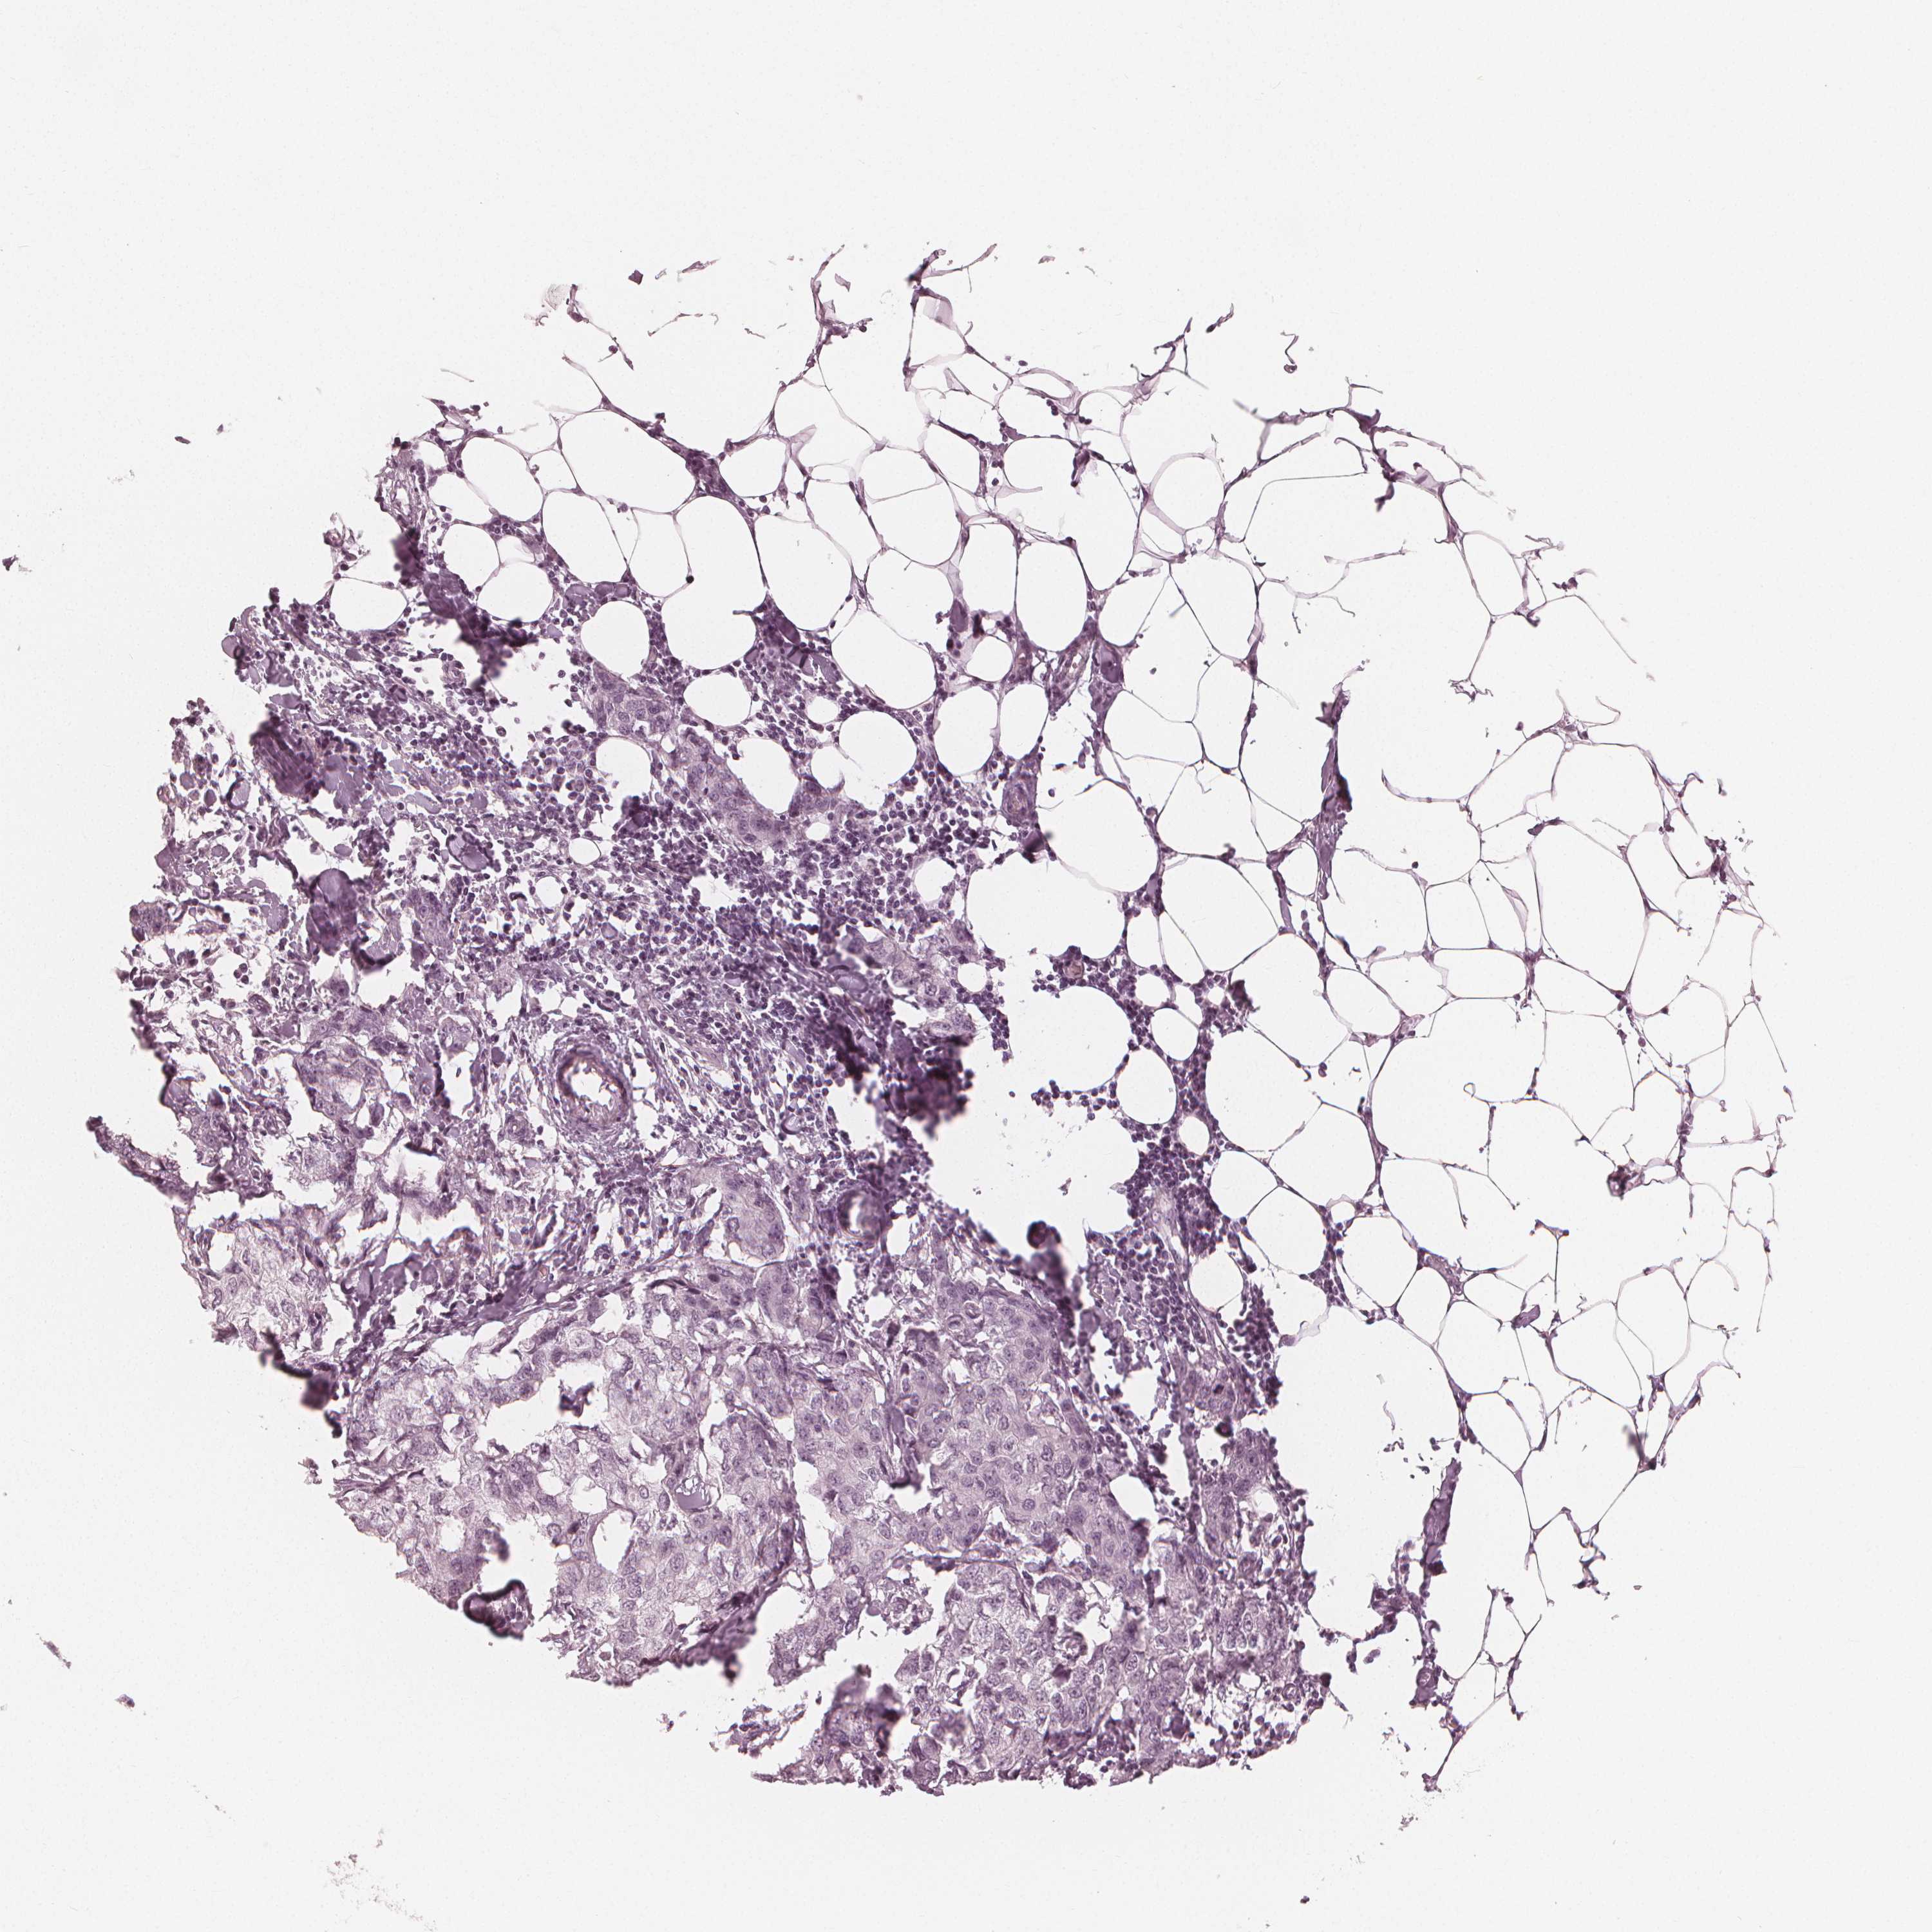

CANCER BREAST CANCER Show tissue menu

Breast cancer

Human cancer